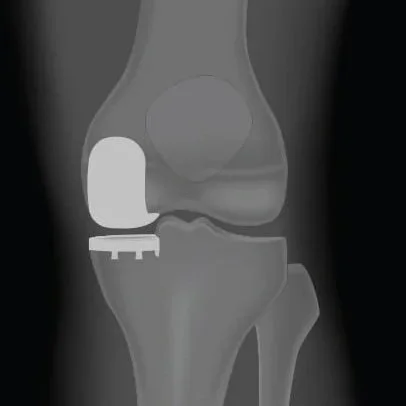

Gianluca Coccioli

ortopedico a Milano